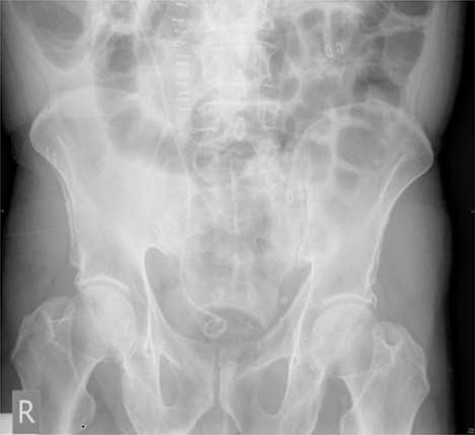

On day three post-procedure, the patient had an abdominal X-ray, which demonstrated correct positioning of the stent (Fig. 3). They were discharged from hospital on day five with planned follow-up for cystoscopic stent removal under local anaesthetic in 6 weeks.

Post-operative plain abdominal X-ray demonstrating acceptable right ureteric stent position.